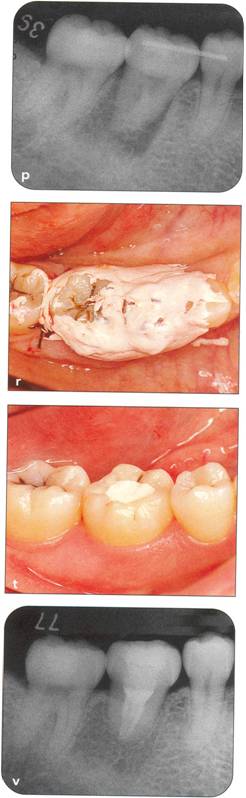

Fi 545e45f g 5-21 Two months after transplantation. |

Fi 545e45f g 5-2m Two months after transplantation. In a developing tooth, pulpal healing is expected. One must, however, carefully watch for signs of resorption or development of bony lesions indicating pulp necrosis. |

Fi 545e45f g 5-2n Eight months after transplantation. Obliteration of the pulp canal from the apex has begun, indicating pulpal vitality. |

Fi 545e45f g 5-20 Two years 5 months after trans. plantation. Total obliteration of the pulp canal has occurred, which is a normal outcome. |

Fi 545e45f gs 5-2p and 5-2q Two years 5 months after transplantation. The donor tooth is restored with composite resin. |